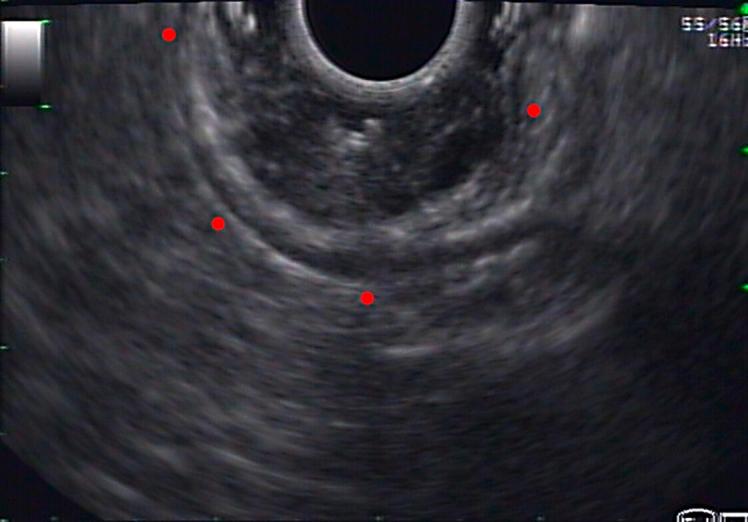

Gastritis Cystica Profunda Presenting as an Ulcerated Subepithelial Lesion.

https://cdn.ncbi.nlm.nih.gov/pmc/blobs/9125/10836860/ce6c9fa2913e/pjg-2024-0031-0001-530669_F01.jpg